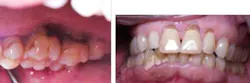

Mrs. High Anxiety after treatment.

Miss Novice after the LANAP protocol.

Mr. First Time after treatment.